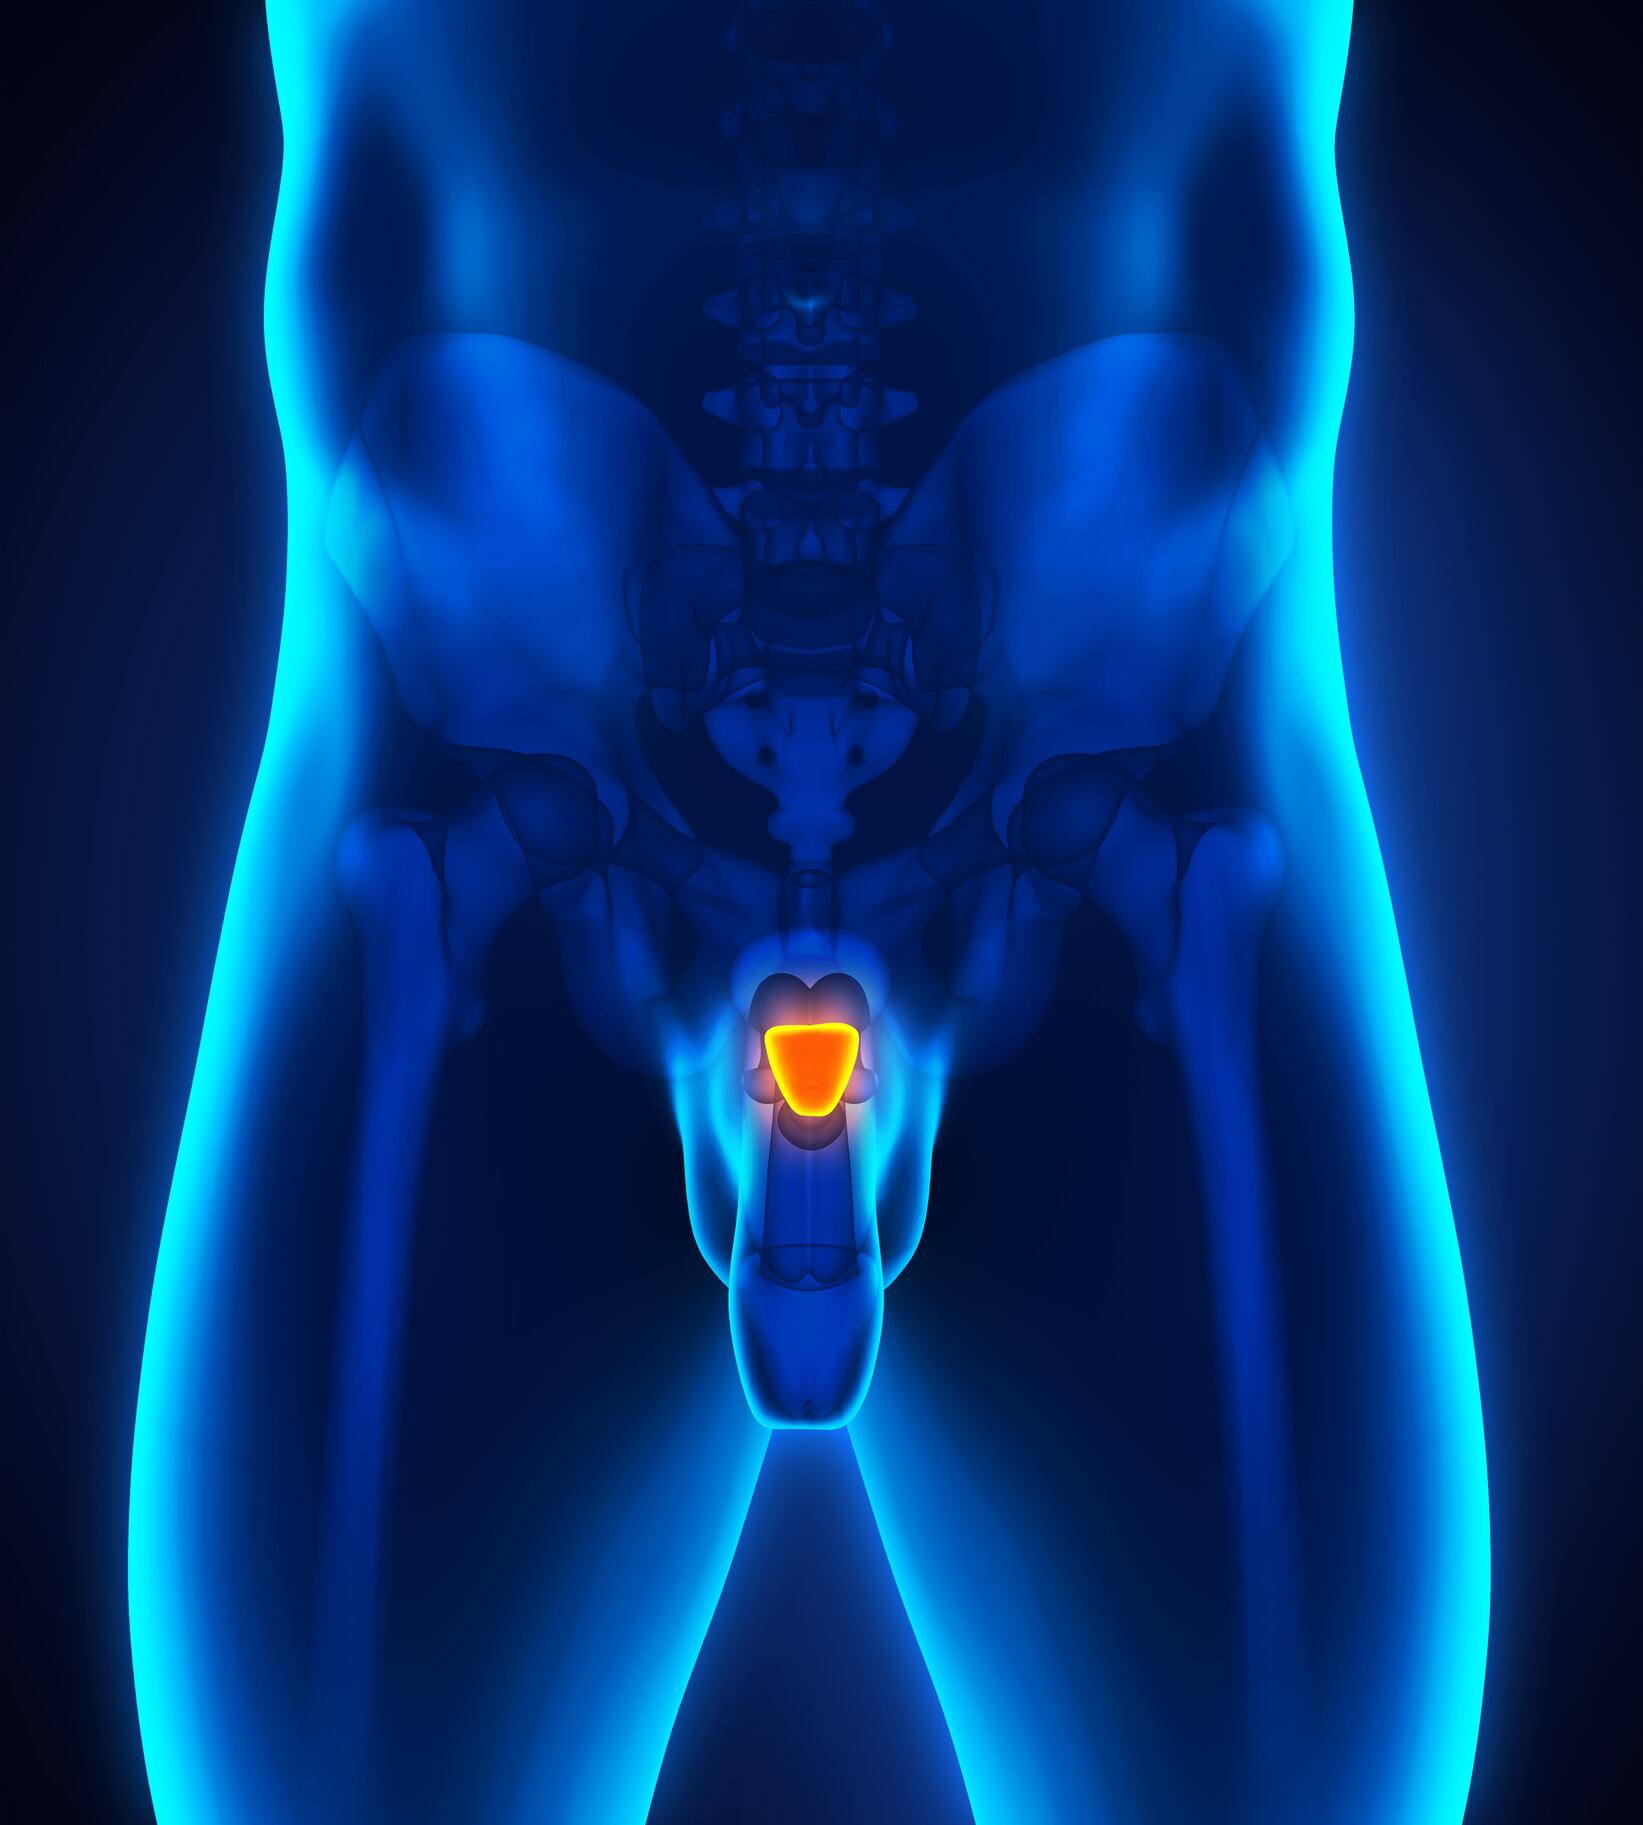

En la actualidad, esta enfermedad sigue siendo la principal causa de muerte a nivel mundial. Específicamente en Colombia, para el año 2022, se identificaron 117.620 nuevos casos y 56.719 muertes por esta causa. Además, según datos de Globocan de 2022, el cáncer de próstata, de pulmón y el mieloma múltiple son algunos de los cánceres con mayor impacto en el país, ya que, durante los últimos 5 años han tenido unas altas tasas de prevalencia.

Por ejemplo, el cáncer de próstata tuvo 39.839 casos, el cáncer de pulmón 8.936 casos y el mieloma múltiple 3.843 casos, que, en comparación con el periodo de 2015, los casos nuevos, los prevalentes y las defunciones han aumentado en 57%, 120% y 222%, respectivamente. Cada una de estas enfermedades requiere de un abordaje individual, según el tipo de patología, el estadio de la enfermedad y las características específicas del paciente.